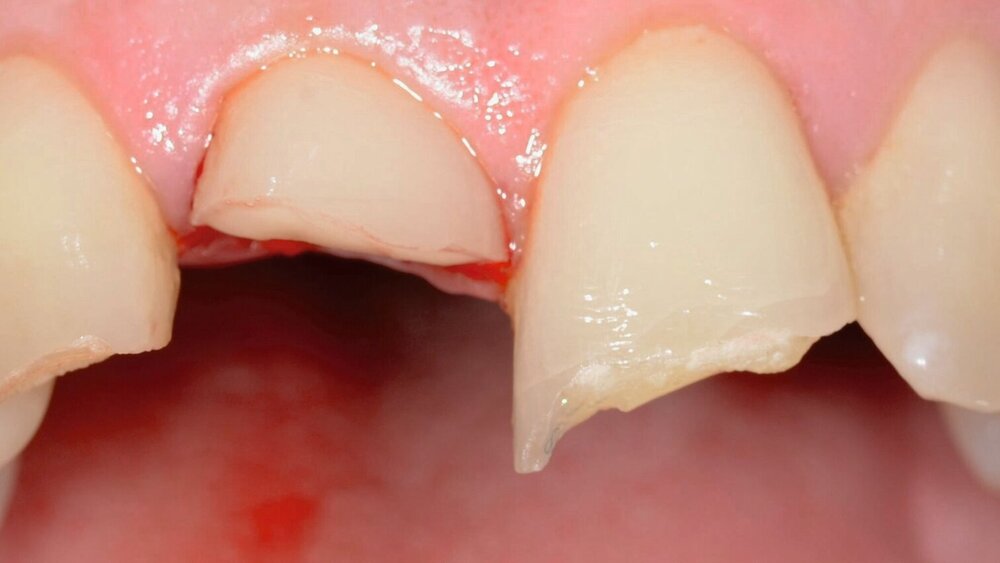

Die zahnärztliche Befundung ergibt koronale Schmelz- und Dentinfrakturen ohne Pulpaexposition an den Zähnen 12 und 21. An Zahn 11 liegt eine ausgeprägtere subgingivale Kronenfraktur vor. Auf dem Weg zur Uniklinik bemerkte der Patient das gelockerte Fragment an Zahn 11, entfernte es selbstständig und lagerte es trocken in einem Taschentuch. Trotz der Nähe der Fraktur zur Pulpa des Zahnes 11 ist diese nicht eröffnet (Abbildung 1).

Das Ziel der Erstversorgung nach Trauma sollte darin bestehen, freiliegende Dentinwunden abzudecken, um eine bakterielle Infektion des Endodonts zu verhindern [Herrmann et al., 2023]. Da die Fragmente der Zähne 12 und 21 nicht auffindbar waren, wird das freiliegende Dentin der beiden Zähne zunächst mit einer adhäsiven Schicht aus Flow Komposit abgedeckt. An Zahn 11 ist das Fragment intakt und repositionierbar, daher kann eine restaurative Versorgung durch adhäsives Reattachment erreicht werden.